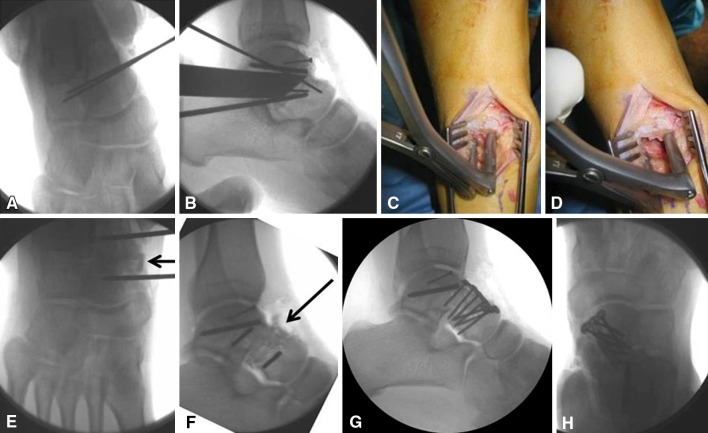

Fig. 1A–H.

After performing a dorsomedial approach, the future osteotomy is marked with two K-wires at the apex of the deformity. (A) Dorsoplantar and (B) lateral radiographs show the ankle intraoperatively. The special distractor is applied between two K-wires to perform (C) distractional and (D) rotational correction of the alar head with regard to the talar body. (E) Dorsoplantar and (F) lateral intraoperative radiographs show the ankle after insertion of a fully cancellous allograft block (arrow). (G) Lateral and (H) dorsoplantar intraoperative radiographs show internal stabilization using a plate to stabilize the distraction osteotomy.

With a tourniquet applied to the ipsilateral thigh, a dorsomedial approach was used. In five patients, implant removal was performed before the correctional osteotomy. A chisel was directed along the fracture plane after implant removal (Fig. 1A–B).

To determine the amount of distraction and rotational correction required of the talar head with regard to the talar body, we used a HintermannTM distractor (Integra LifeSciences Corporation, Plainsboro, NJ, USA), which was applied between two K-wires, and allowed manipulation of the distracting forces and rotational movement until an appropriate correction of the forefoot was achieved (Fig. 1C–D). Once the desired position was achieved, the size of the graft was determined as measured by a ruler.

Human cancellous allograft blocks (Tutoplast®; Tutogen Medical GmbH, Neunkirchen am Brand, Germany) were used on a routine basis for interposition as the required size of graft was not considered critical for revascularization (Fig. 1E–F). Two patients requested the use of their own bone, so a tricortical autograft from the iliac crest was used.

As a standard approach, two screws provided the required stability after the correcting osteotomy and graft insertion. However, if the bone graft did not provide enough distraction stability (eg, against compressive forces), the use of a buttress plate was considered. Analogously, if the head fragment was too short and thus the screw purchase alone was insufficient to provide stability against rotational forces, an additional plate was considered (Fig. 1G–H).